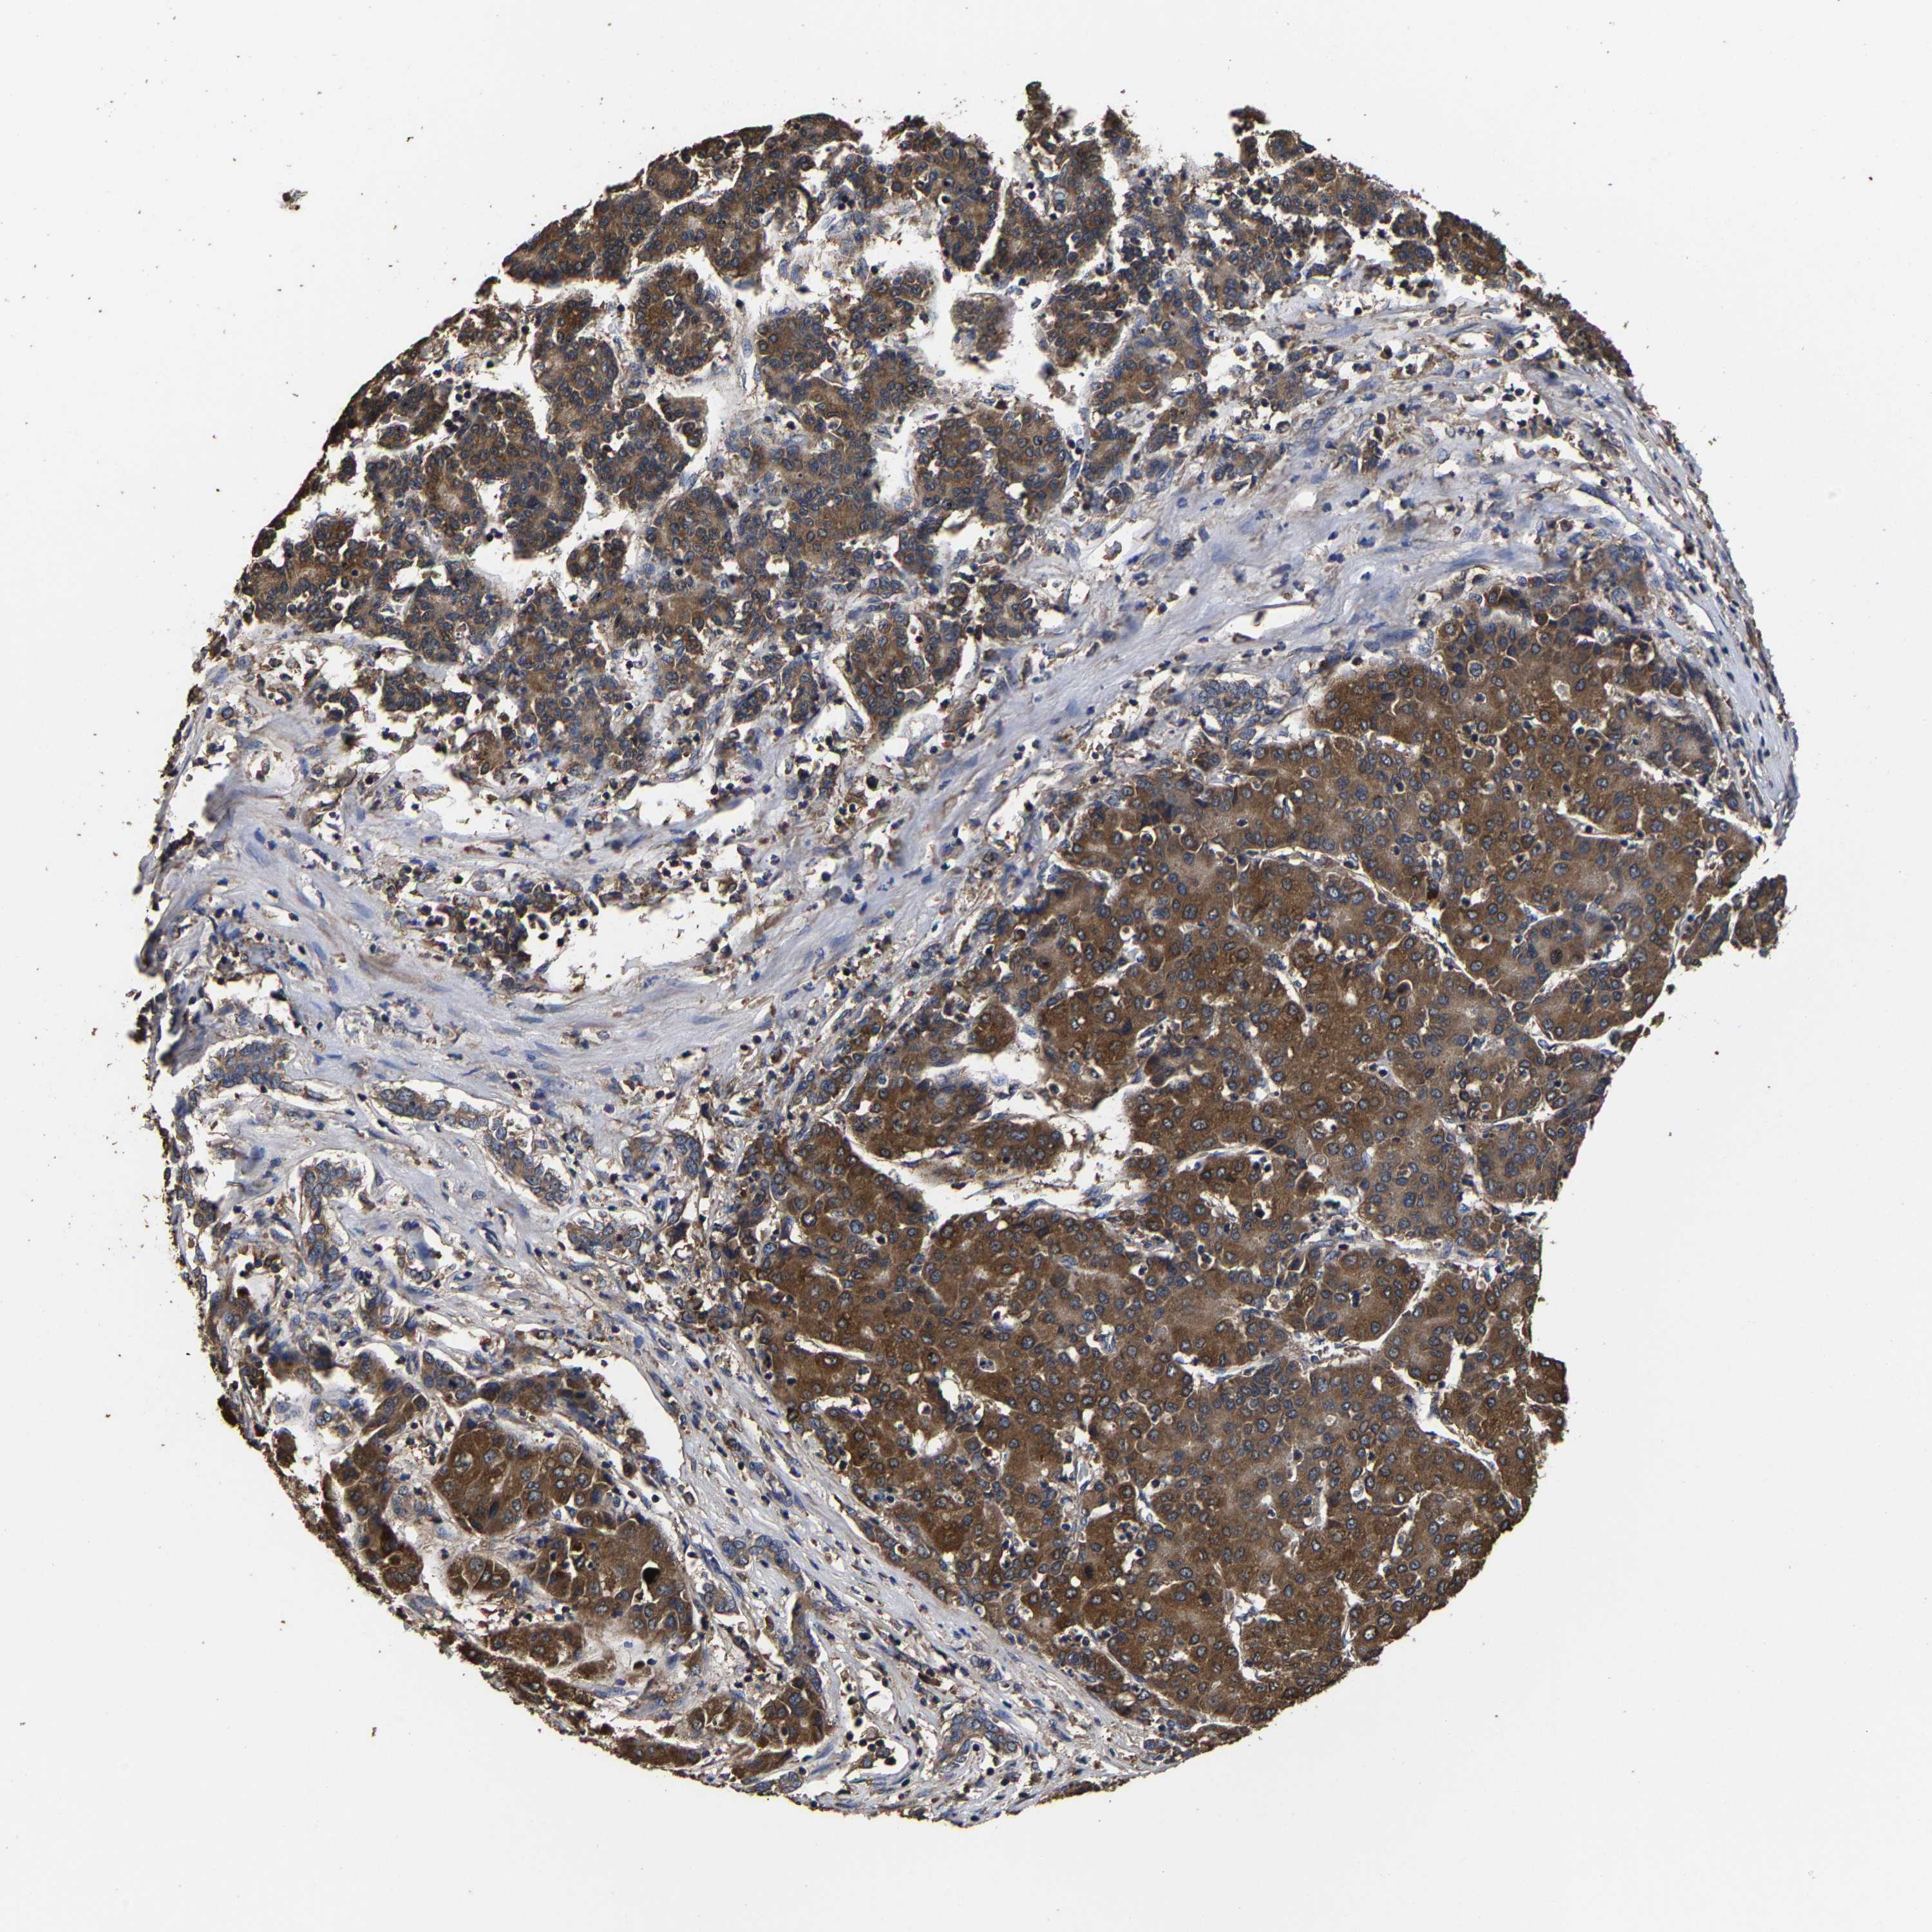

LIVER CANCER